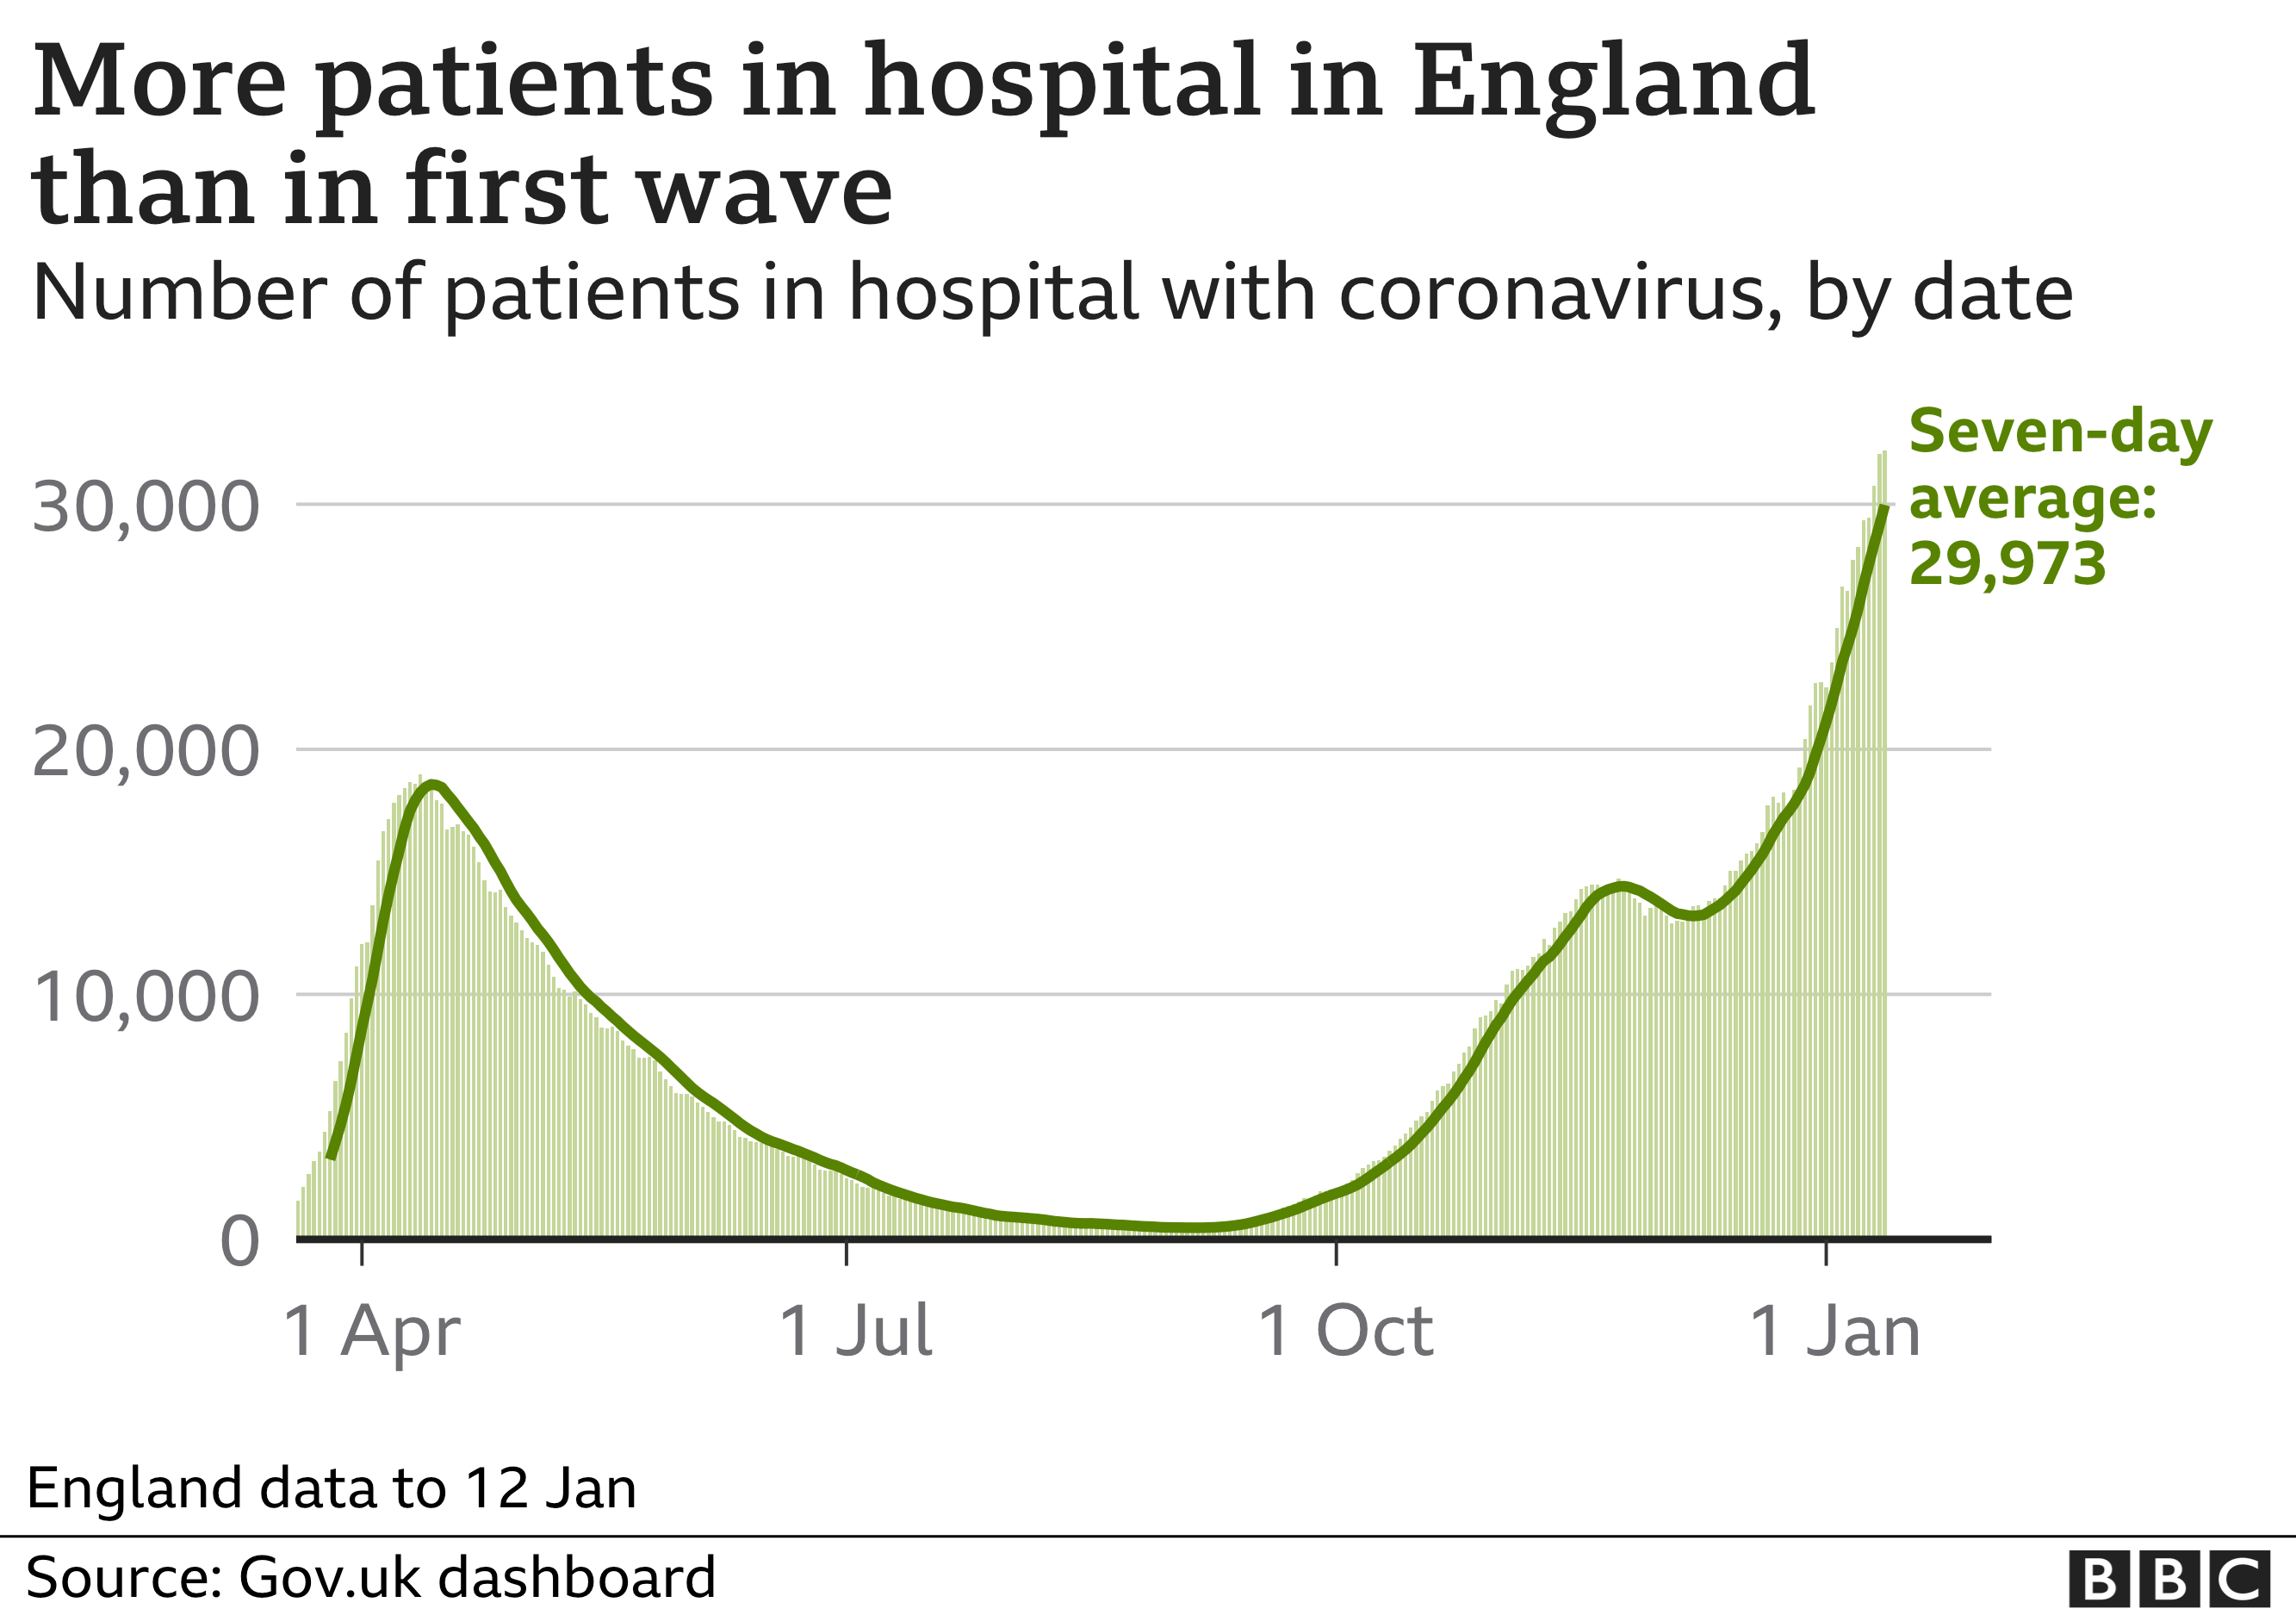

It comes after a surge in Covid patients in recent weeks.

One in three patients in hospital have the virus – and at some sites it is more than half.